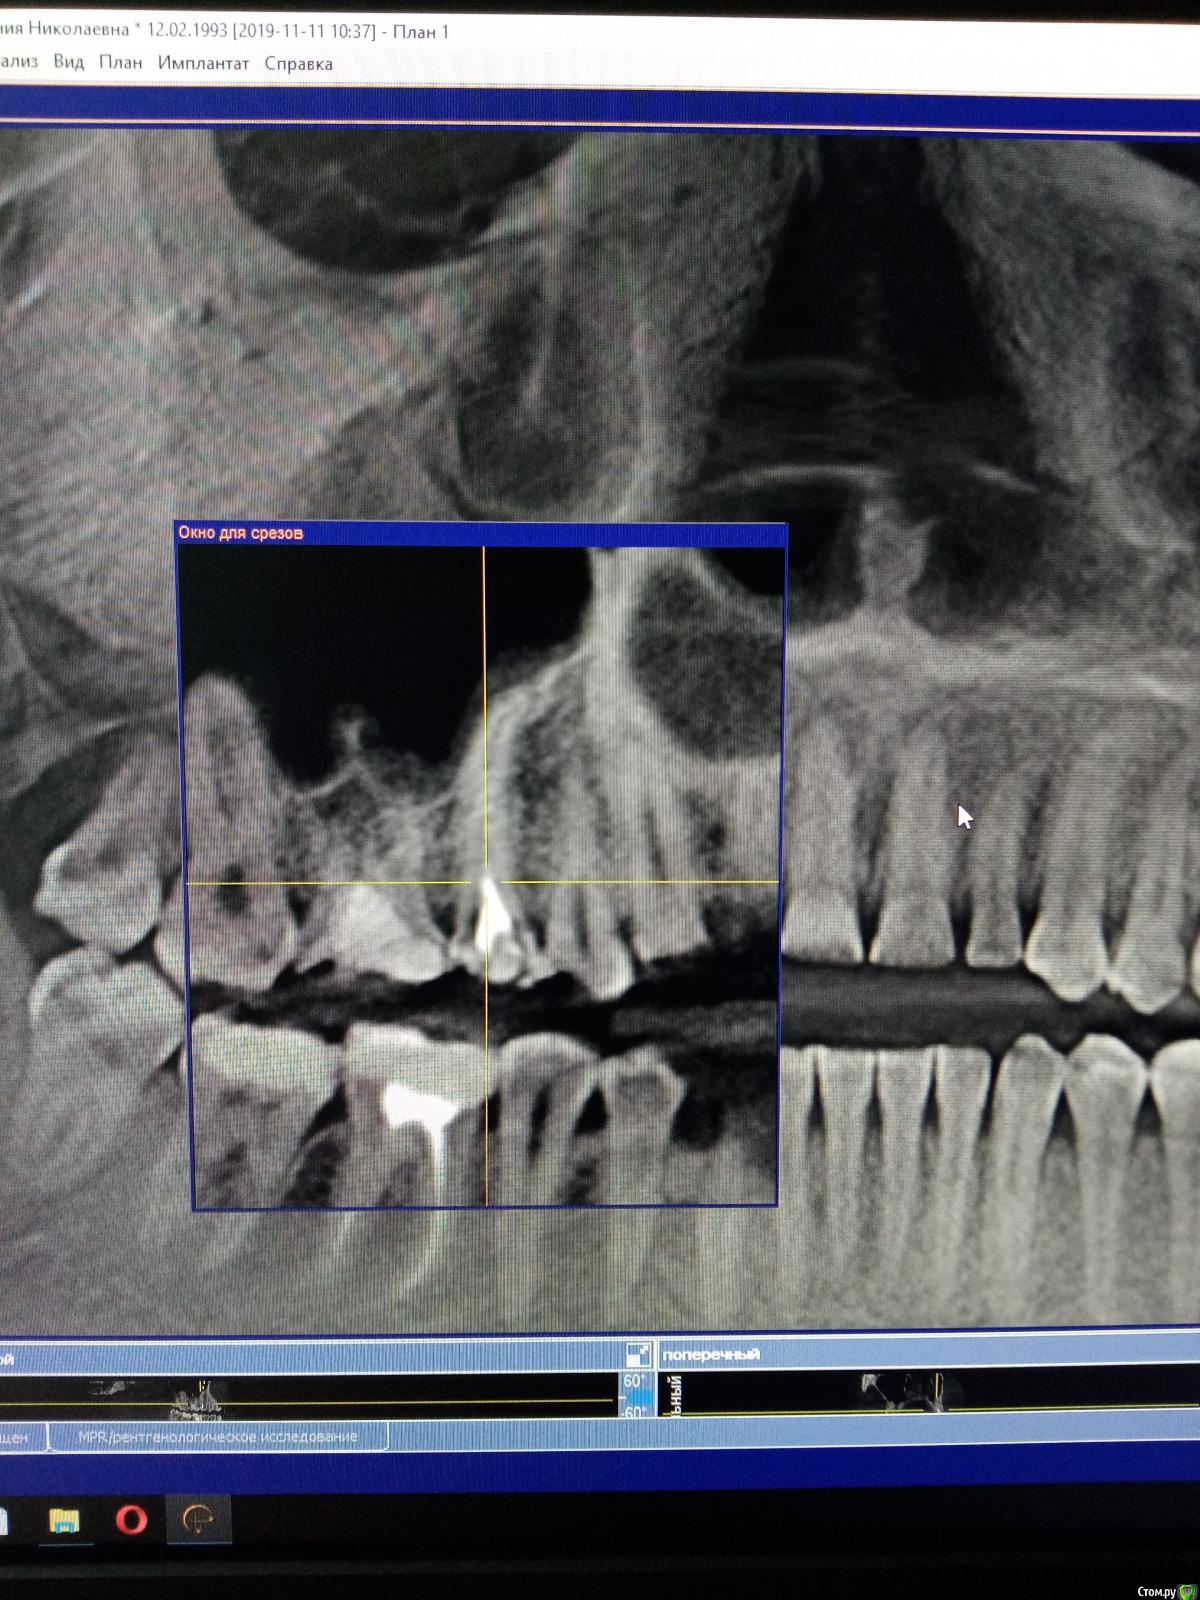

Raimar Опубликовано 18 ноября, 2019 Поделиться Опубликовано 18 ноября, 2019 Подскажите, как можно произвести эндодонтическое лечение? Нужно ли проходить дополнительные канальцы? Зуб 1.5 Ссылка на комментарий

Raimar Опубликовано 18 ноября, 2019 Автор Поделиться Опубликовано 18 ноября, 2019 Я так сначала и думал сделать,если честно), подскажите пожалуйста как можно пройти эти канальцы, у меня файлы упираются Ссылка на комментарий

vse32 Опубликовано 18 ноября, 2019 Поделиться Опубликовано 18 ноября, 2019 у меня файлы упираются На какой глубине упираются?Вероятно ступень нарезана. Расширяете сильно до ступени, подгибаете тоненький файл в сторону изгиба и пытаетесь в него зайти. Далее пытаемся расширить и сгладить ступень. С микроскопом конечно все удобнее, но и без него во многих случаях вполне реально. 1 Ссылка на комментарий